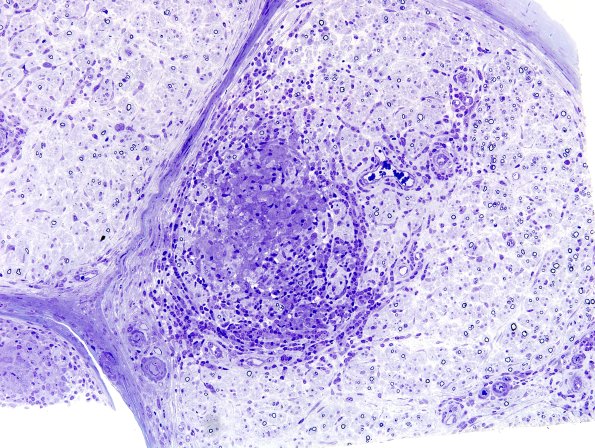

Washington University Experience | PERIPHERAL NEUROPATHY | 10 INFECTION | 5 Leprosy - Other | 1B2A Leprosy, tuberculoid (Case 1) Plastic 19A

1B2A,B Although the density of axons is decreased, the fascicles are enlarged resulting in a more modest overall axon loss. Many of the axons show thinned myelin but relatively few regenerative clusters suggesting a demyelinated component. (plastic sections)